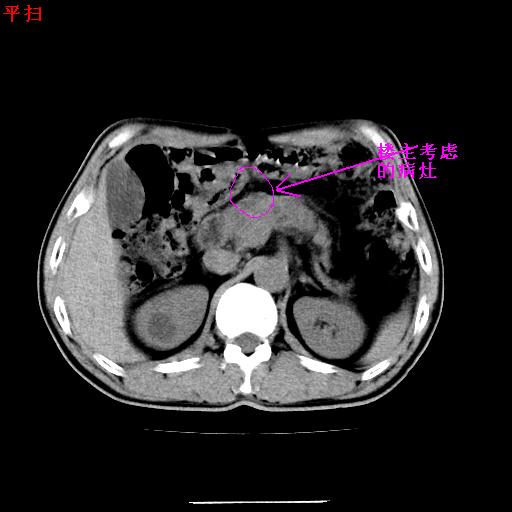

病灶确实存在,请看以下2幅图片:

另外,胰腺体部密度在平扫和增强时均不太均匀,似有数个小的囊状低密度区存在。不知道增强时其他期如何?应该高度警惕为转移性病变。